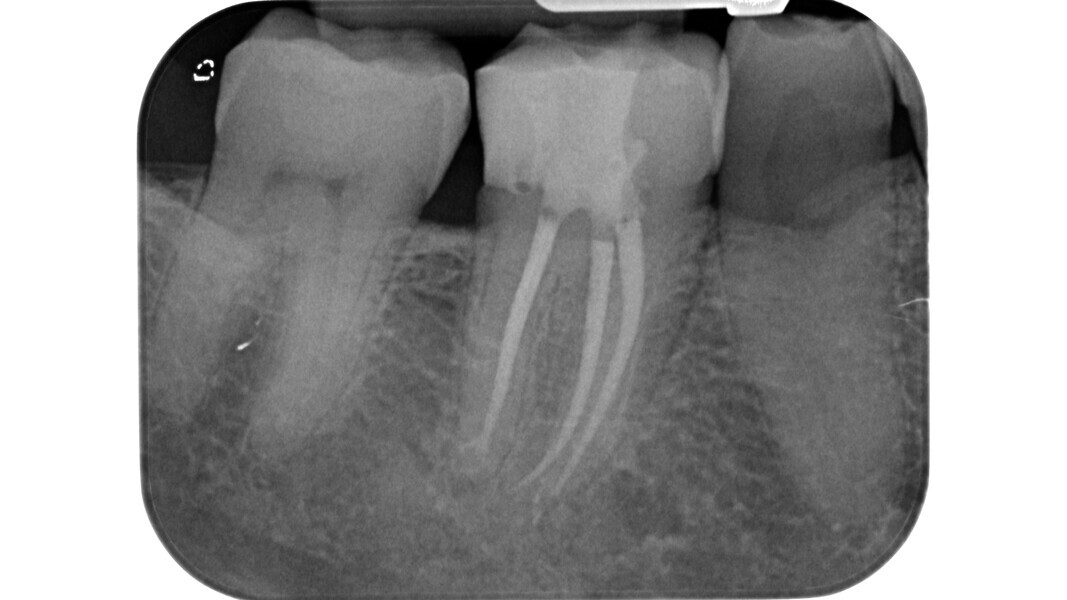

Le principe du diamant fait référence à l’utilisation d’un certain type de fraise diamantée pour la phase de pénétration, en particulier dans les molaires supérieures et inférieures, ainsi que dans les prémolaires supérieures biradiculées. Deutsch8–9 associe des mesures morphologiques à la relation entre la surface occlusale, la hauteur, la position du plafond et du plancher de la cavité dans les dents pluriradiculées. Dans ces éléments, le plafond de la cavité pulpaire est situé au niveau de la JAC.

Dans les molaires, la distance entre la pointe d’une cuspide et le plafond de la cavité pulpaire est d’environ 6,3 mm, tandis que dans les prémolaires supérieures, elle est de 6,94 mm. La cavité pulpaire a une hauteur d’environ 1,5 à 2 mm et la distance moyenne entre le plancher de la cavité et la furcation est d’environ 3 mm (Tableau 1) (Fig. 13).